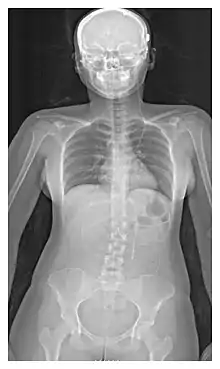

The location of the shunt is determined by the neurosurgeon based on the type and location of the blockage causing hydrocephalus. All brain ventricles are candidates for shunting. The catheter is most commonly placed in the abdomen but other locations include the heart and lungs.[10] Shunts can often be named after the route used by the neurosurgeon. The distal end of the catheter can be located in just about any tissue with enough epithelial cells to absorb the incoming CSF. Below are some common routing plans for cerebral shunts.

| Route | Location of fluid drain |

|---|---|

| Ventriculo-peritoneal shunt (VP shunt) | Peritoneal cavity |

| Ventriculo-atrial shunt (VA shunt) | Right atrium of the heart |

| Ventriculo-pleural shunt (VPL shunt) | Pleural cavity |

| Ventriculo-cisternal shunt (VC shunt) | Cisterna magna |

| Ventriculo-subgaleal shunt (SG shunt) | Subgaleal space |

| Lumbar-peritoneal shunt (LP shunt) | Peritoneal cavity |